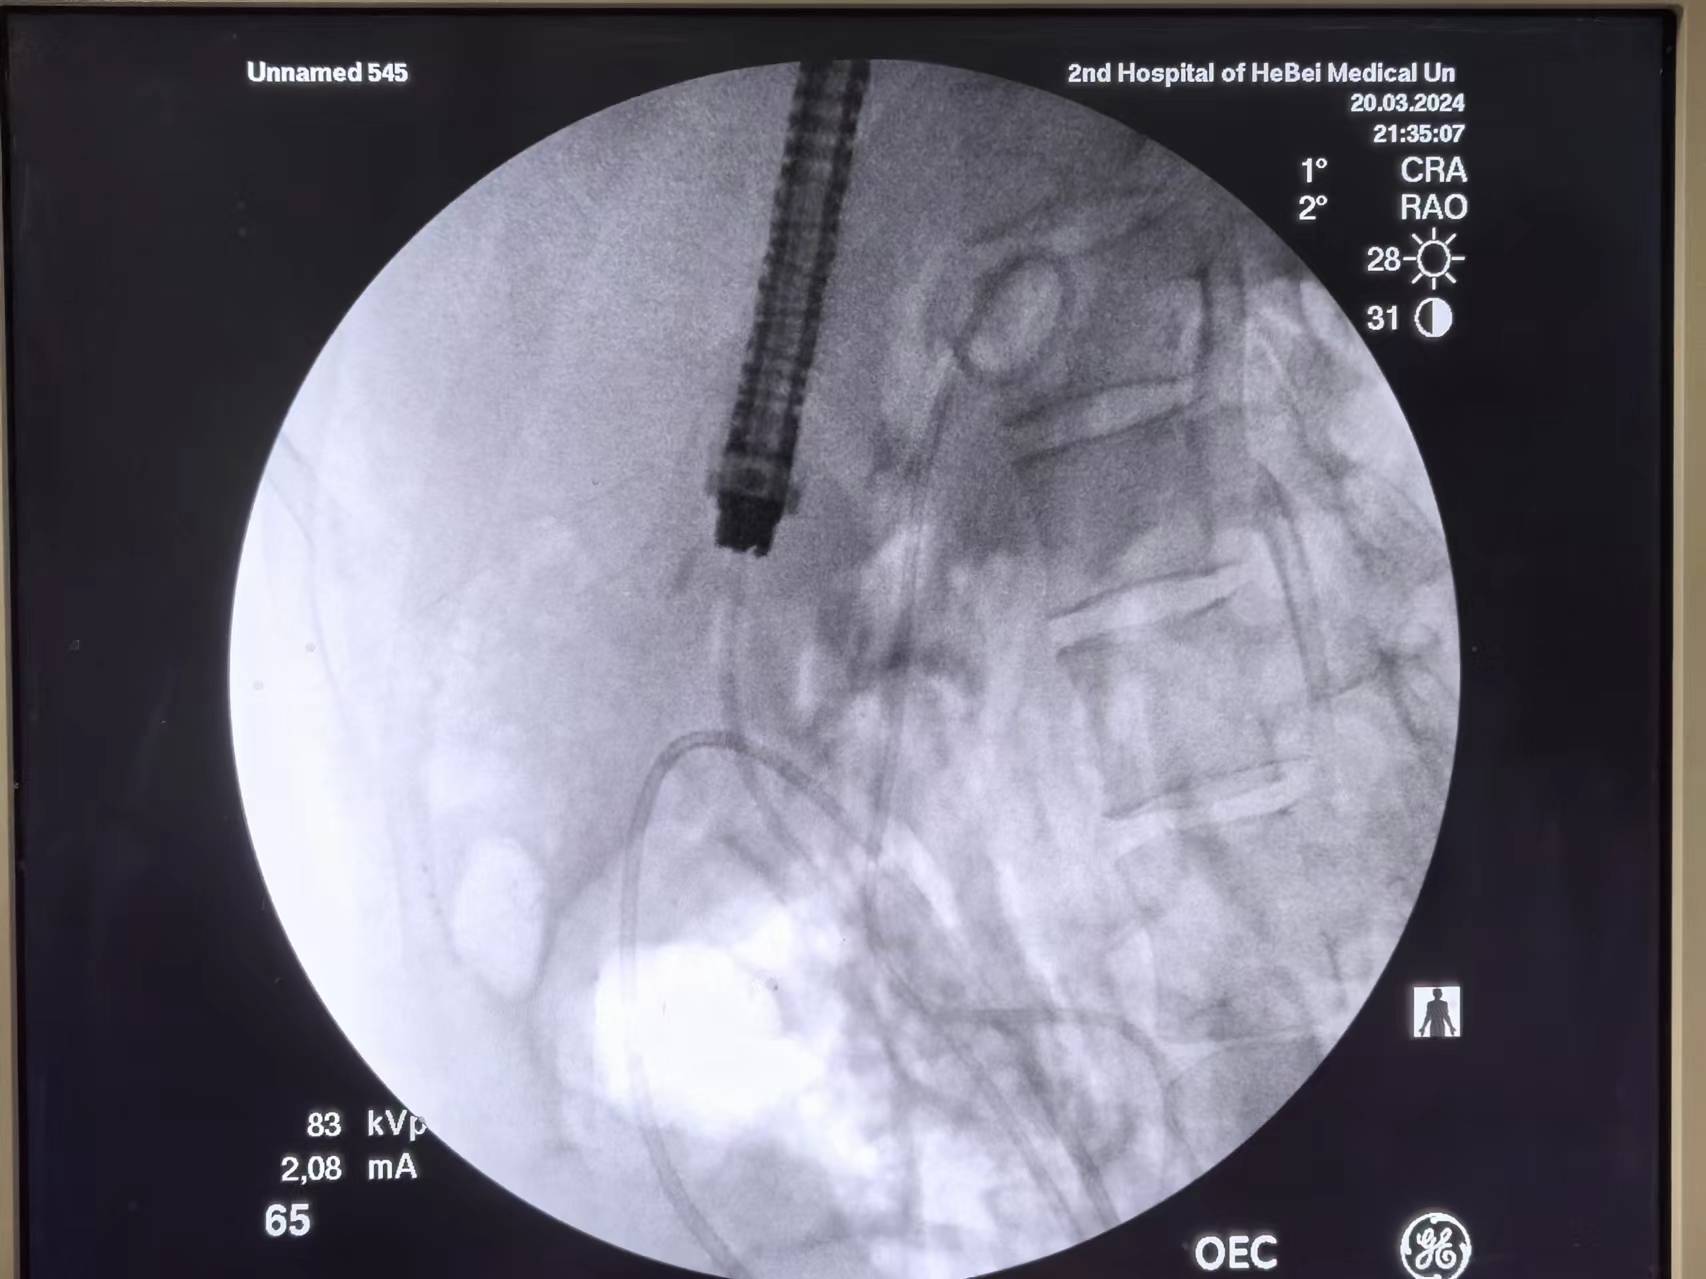

进入导丝

跟刀,打造影剂。其实也仅仅是刀头堵住了开口

由于开口过于狭窄,弓型切开刀不能进入,换囊肿切开刀(环形)切开。然后应用扩张水囊扩张

网篮取石

置入鼻胆管